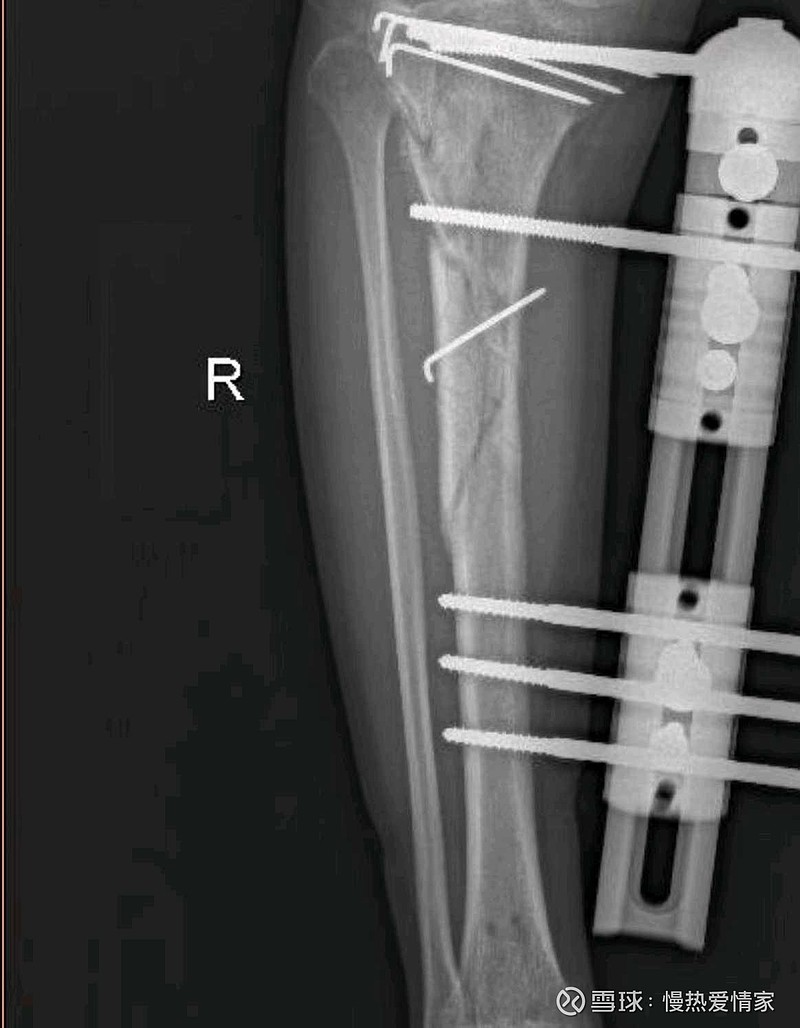

什么时候上市啊,天天打抗凝针,听医生说一针nl003能管用一年